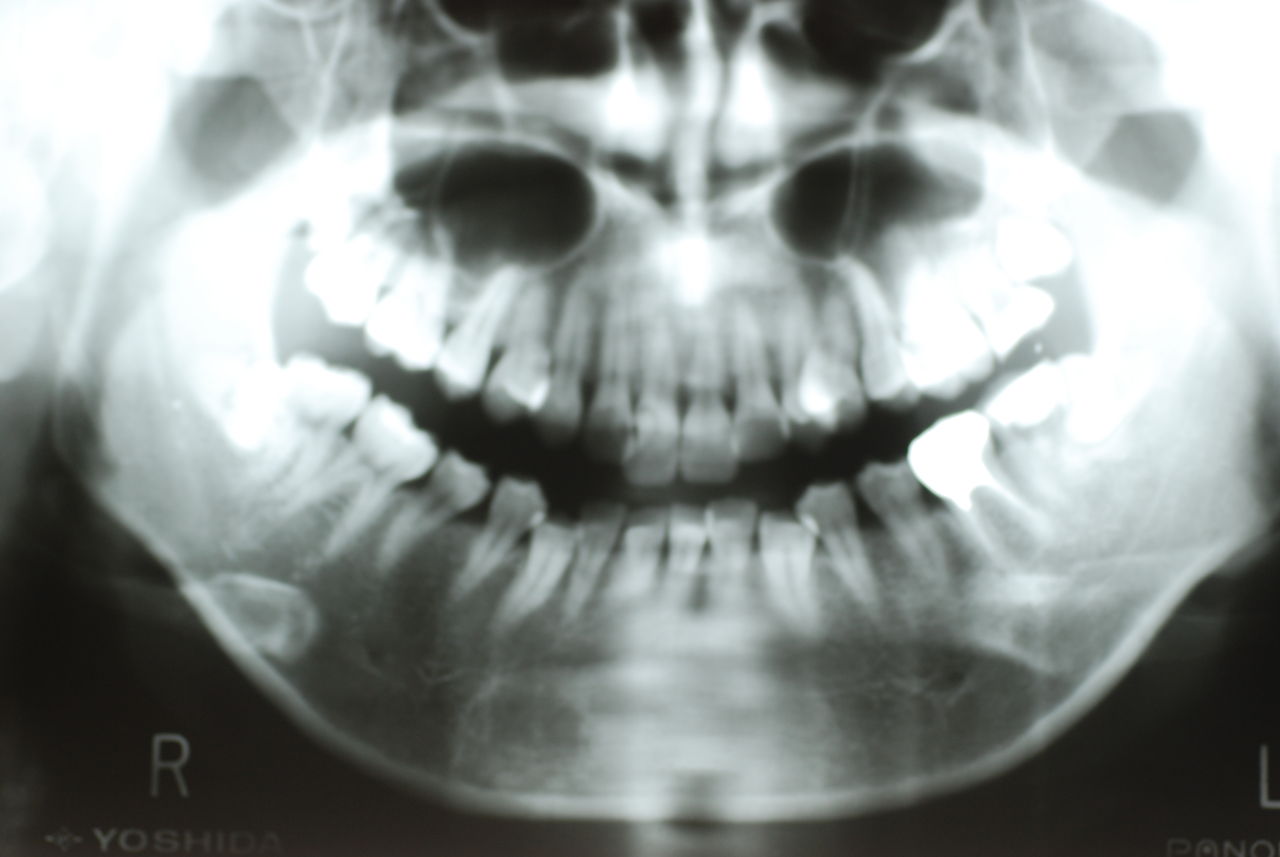

70代の患者ですが上の歯は残根一つ全て歯は無し。

下顎、殆ど歯はなく歯周病で抜けそうな歯と虫歯だらけの歯、適合の悪い銀歯が入っていてそれも虫歯と歯周病で危ない状態でした。入れ歯は下の入れ歯は入れたことがないようです。(ため息)痛くて入れたことがないそうです。

左下の歯は歯の中の治療も?ですごい歯周病を患い歯茎の穴(ポケットと呼ばれるところ)から膿が出ているのです。ばい菌と毒素で骨が溶けて深い穴ができてそこにまたバイキンと毒素がたまるという悪循環ができているのですね。